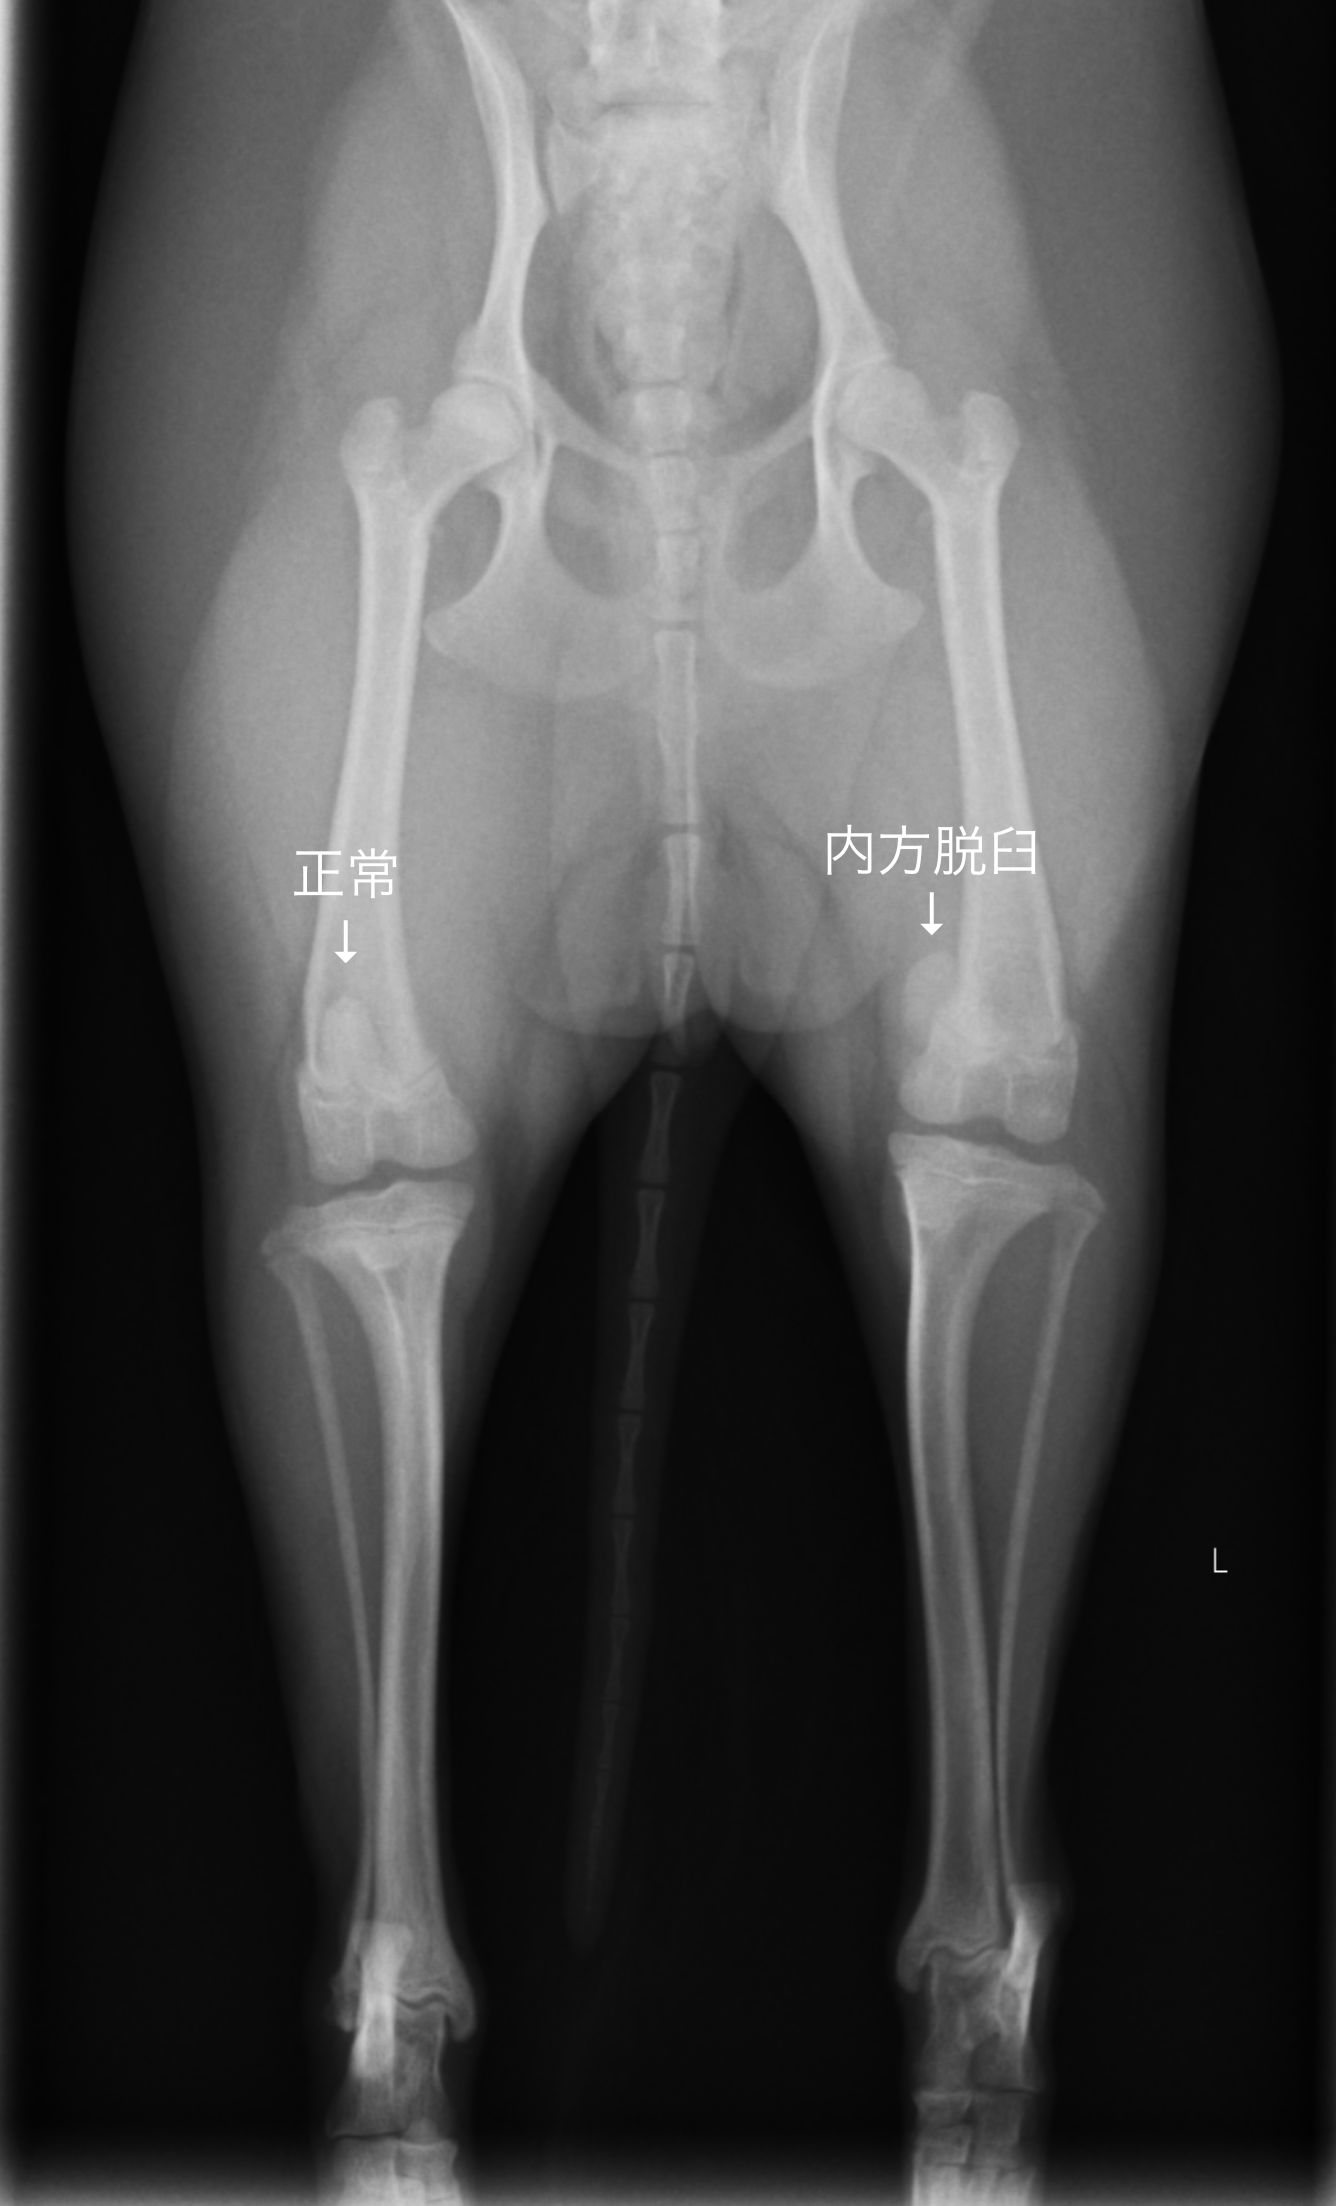

・レントゲン検査(膝蓋骨の位置、骨の変形を見る)

●膝蓋骨脱臼について 膝蓋骨という膝のお皿が正しい位置から脱臼してしまう病気で、多くは内側にずれてしまいます。

膝蓋骨脱臼にはいくつか種類があり、シングルトンのグレード分類により分けることが出来ます。